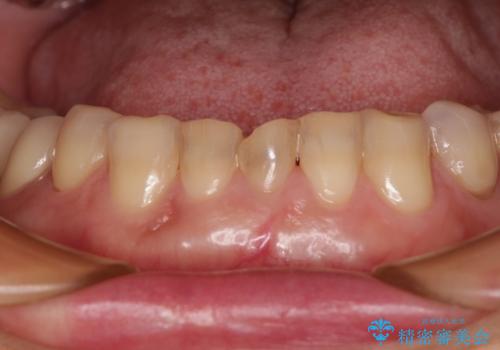

- 割れていると言われて放置してしまった歯や、前歯のデコボコなどが気になるとのことで来院された患者様です。

左上の歯は割れてしまっており、抜歯のうえインプラント治療が必要であり、他にも抜歯の必要な歯がある状態でした。

上顎はほぼ全ての歯をセラミッククラウンにて補綴治療を行う必要があるため、気になるデコボコや深い咬み合わせを改善するために下顎と上顎の臼歯部の矯正治療を行うこととしました。

過蓋咬合(下顎前歯が隠れてしまうほどの深い咬み合わせ)のため、スムーズに歯が動かず矯正治療に時間がかかりましたが、無事に仕上げることができました。